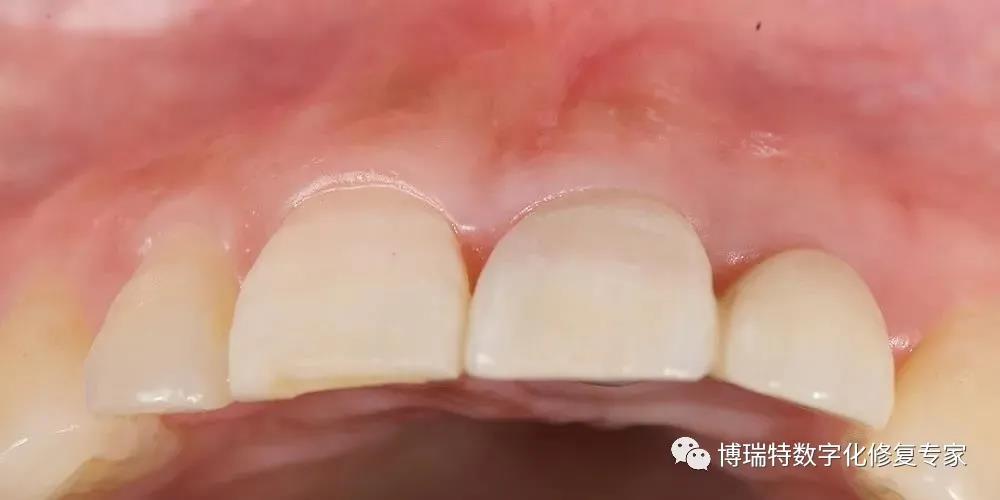

最终修复

8226; 临时冠戴入3个月后,可见21、22间牙龈乳头冠向生长,前牙区龈缘对称,软组织获得良好的穿龈轮廓形态;

8226; 为了诱导11、21间龈乳头继续冠向生长,扩大11、21龈外展隙;

8226; 两周后,戴入最终修复体;

8226; 牙冠形态颜色协调,轮廓及龈缘形态基本协调对称,红白美学效果较理想;

8226; 咬合微调至正中及侧方无干扰后抛光。